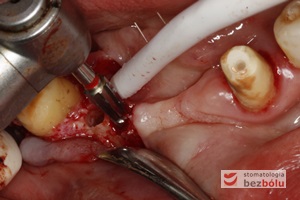

Piesosurgery - przyjazne dla pacjenta i chirurga - wstępne opracowanie łoża implantów za pomocą piesosurgery (piezochirurgia)

Piesosurgery – przyjazne dla pacjenta i chirurga – wstępne opracowanie łoża implantów za pomocą piesosurgery (piezochirurgia)

Opracowanie łoży implantów - poszerzanie łoży implantów oraz zagęszczanie kości przy użyciu techniki osteotomowej

Opracowanie łoży implantów – poszerzanie łoży implantów oraz zagęszczanie kości przy użyciu techniki osteotomowej

Ostateczne opracowanie kształtu łoża implantu - użycie sekwencji wierteł - ocena równoległości łoży implantów

Ostateczne opracowanie kształtu łoża implantu – użycie sekwencji wierteł – ocena równoległości łoży implantów

Wprowadzenie implantów - implant Ankylos umożliwia wprowadzenie pod wyrostek co zapewnia wysoką stabilizację

Wprowadzenie implantów – implant Ankylos umożliwia wprowadzenie pod wyrostek co zapewnia wysoką stabilizację